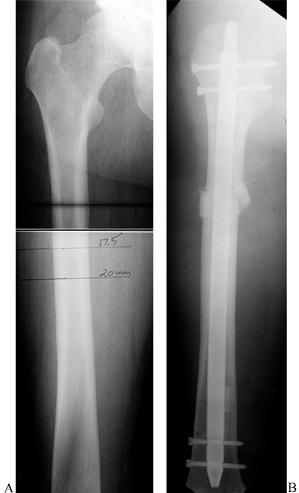

Winquist et al. (44) (Fig. 30.9, Fig. 30.11).

Although the technique shortens the patient’s overall stature, and in

large corrections will affect overall body proportions, it is

technically a much simpler technique than lengthening, and it offers

the advantages of immediate weight bearing, early union, and early

return to function (Fig. 30.12).

Figure 30.12. A: Preoperative AP radiograph showing the planned osteotomy sites to equalize a leg-length discrepancy of 25 mm. B: Postoperative AP radiograph showing correction of the leg-length discrepancy with a locked Alta nail for fixation.

|

Determination of the actual leg-length discrepancy can be difficult. I

have not found scanograms to be consistently reliable, so I use them

only for confirmation of other measurements. The best technique is to

place blocks under the short leg of the standing patient to level the

pelvis. Rely on your judgment of the correction of the discrepancy and

the patient’s feelings about the correction. Try to obtain a level

pelvis and take into account any distortion of the pelvis that may be

present from old trauma or developmental or congenital abnormalities.

Then confirm the clinical measurement by taking an AP radiograph of the

pelvis with the patient again standing on enough blocks to correct the

leg-length discrepancy. Use either the film or a horizontal marker to

establish a level plane of reference. Take full-length AP and lateral

radiographs of the femur to be shortened to ensure that there is no

abnormality that would contraindicate shortening.

additional weeks will be fully weight bearing without assistive devices

(Fig. 30.12).